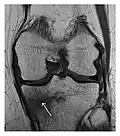

- a

- b

Figure 14: Subcapital insufficiency fracture in a 55-year-old man with a left hip pain without a history of trauma. Anteroposterior and Lauenstein view radiographs centered on the left hip do not show an obvious fracture line, but mild acetabular osteophytosis was noted consistent with hip osteoarthritis (not shown). (a) Coronal T1-weighted MRI shows a linear low-signal band through the femoral neck corresponding to a fracture line (arrowheads). (b) Bone scintigraphy shows focal uptake (arrow) corresponding to the fracture.[1]